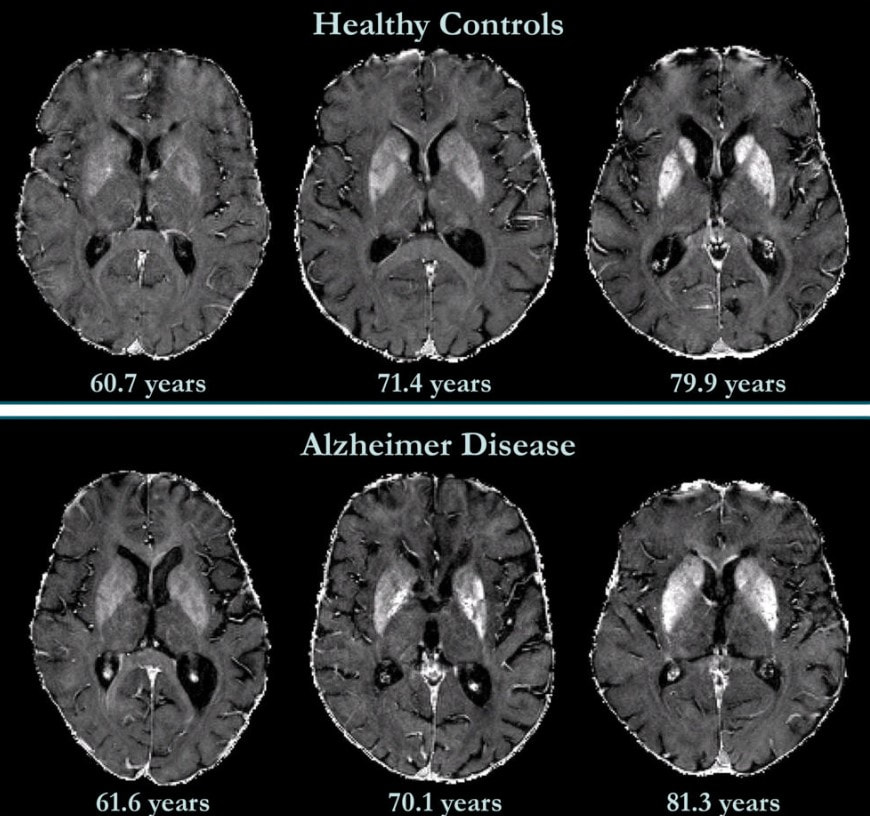

Альцгеймера поразило, что симптомы, обычно присущие глубокой старости, проявились у сравнительно молодой женщины. Он подробнейшим образом документировал её угасание в течение нескольких лет, а когда Августа скончалась в 1906 году, провёл вскрытие. Под микроскопом он увидел то, чего раньше не замечал ни один учёный: мозг пациентки был буквально усыпан мельчайшими “просяными зёрнышками” и опутан плотными клубочками повреждённых волокон. Так впервые были описаны две главные “визитные карточки” недуга – амилоидные бляшки и нейрофибриллярные клубки.